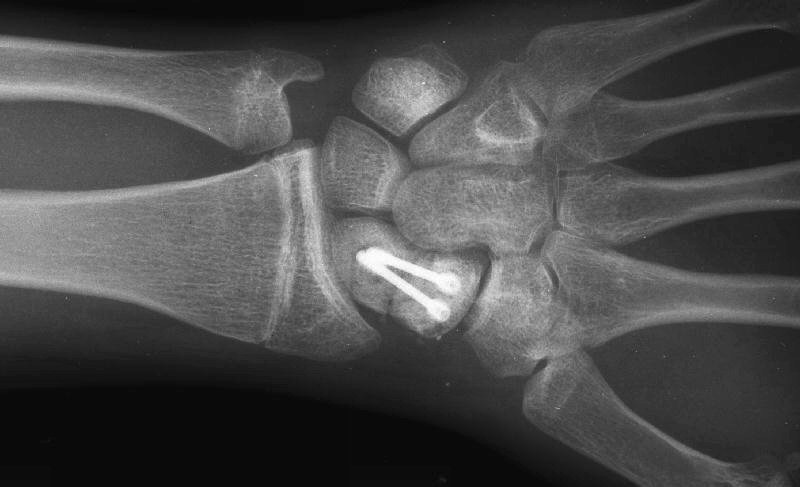

Clinical Example: Revision scaphoid nonunion with hardware removal, bone graft and two Herbert screws

This 19 year old had been treated elsewhere with an accutrac screw for a displaced scaphoid fracture. He was noncompliant with immobilization after surgery, and developed a painful nonunion.

The nonunion was reconstructed by removing the hardware, iliac bone graft and two Herbert screws placed through new paths. Cancellous bone was packed into the old screw hole.